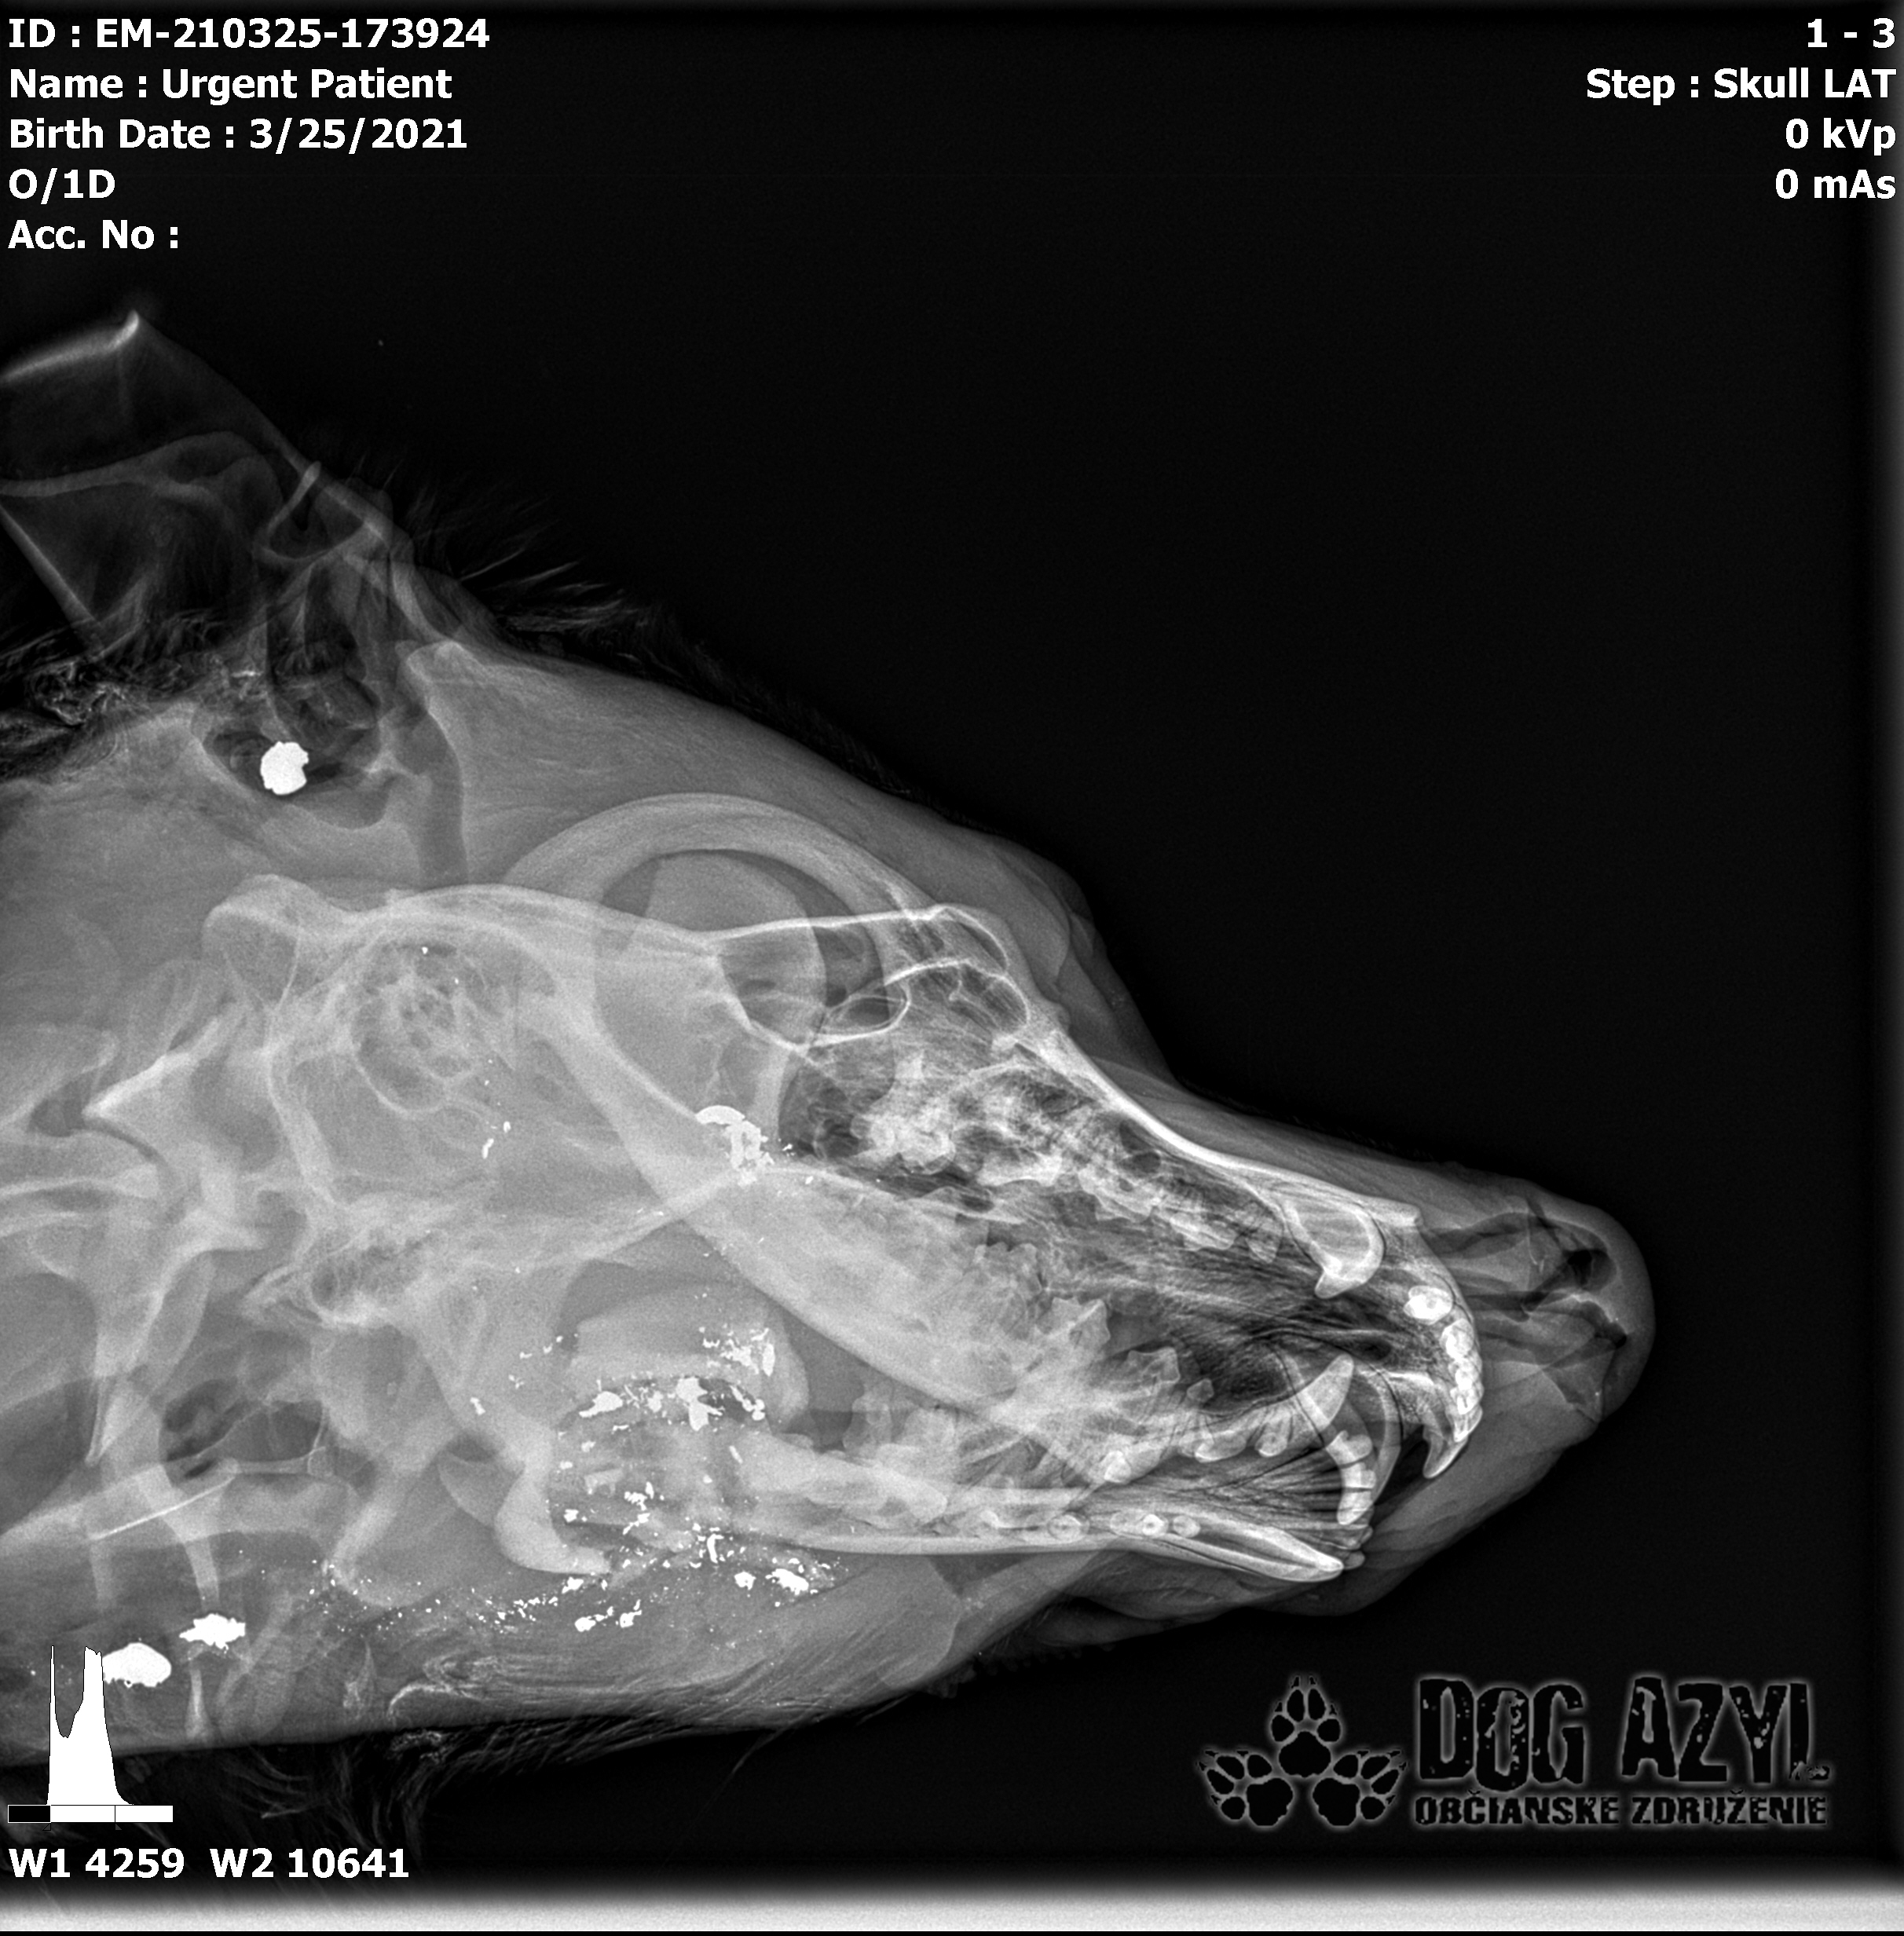

Ona ležala na ľavo, on na pravo od zavesenej šunky, ktorá mala zrejme slúžiť ako návnada, aby sa terče nehýbali.. Uprostred ničoho, bez svedkov, bez dôkazov... Pár kvapiek krvi na ceste.. Ona to schytala jedinou ranou do srdca.. On má roztrieštenú sánku, schytal to do hlavy..

/Strašne to chcem dopísať tak, aby to bolo čitateľné a pochopiteľné, ale celá sa klepem od zlosti a nevidím cez slzy.../ Lebo Ona už meno nikdy nebude mať.. On dostal meno Baris a bojuje o život!!! Má dolámanú sánku a je v šoku!!! Dostal prvú pomoc, analgetiká a priorita bola znížiť jeho teplotu z 41,4°C!!!

Ústami nevie pohnúť, jazyk si nevie ovládať a tak sa sám nedokáže schladiť ani napiť. Podľa RTG sú srdiečko a pľúca v poriadku, ale vôbec nemá vyhraté!!! Niekto chcel Barisa zlikvidovať, ale my za neho budeme bojovať do posledného dychu!!! Zajtra bude prevezený na veterinárnu kliniku Sibra centrum, kde ho čaká team špecialistov z oblasti chirurgie, neurológie a ortopédie. Ak je čo i len najmenšia nádej, že Baris bude môcť žiť, tak BARIS BUDE ŽIŤ!!!